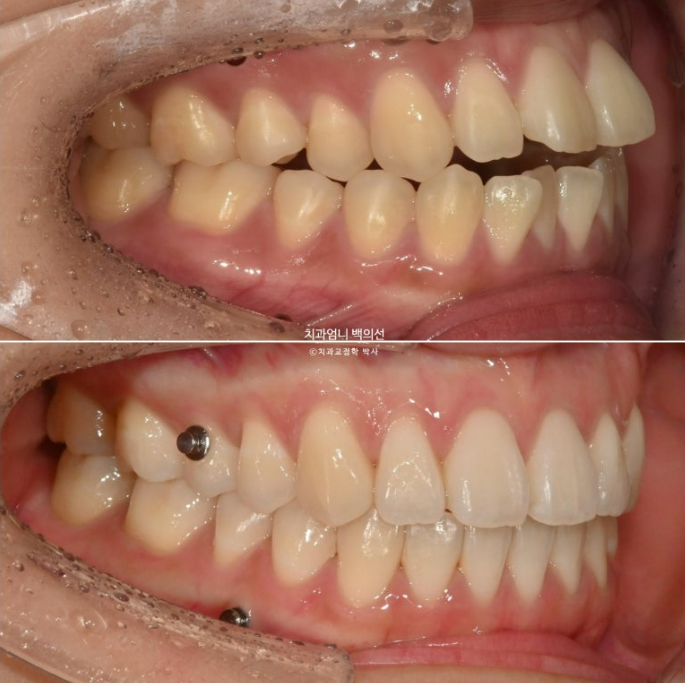

안모 변화 보겠습니다.

깔끔한 스마일라인과 입동굴

적절한 앞니 각도

이제 어금니 함입에 의한 하악골 자가회전 효과를 보겠습니다.

실눈 뜨고 보면 처음에 비해 하관이 약간 짧아지며 턱끝이 약간 나오고 도툼해졌습니다.

발치했으면 큰일날 뻔했습니다.